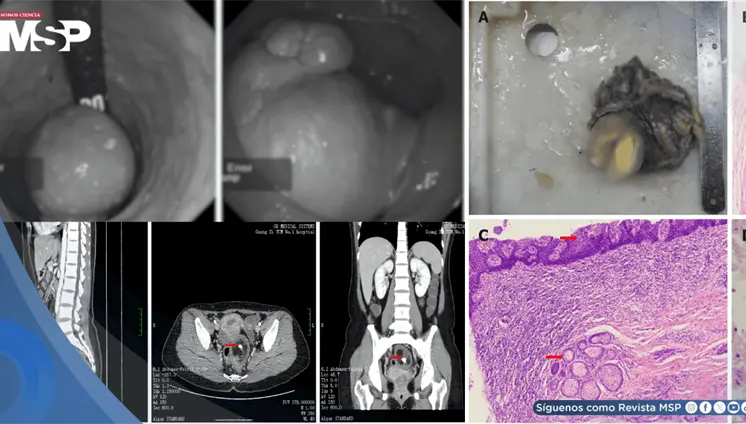

La paciente presentó cambios en el hábito intestinal y sangrado rectal con imágenes compatibles con lesiones estenosantes, inicialmente sospechosas de neoplasia sincrónica.

La pseudomelanosis vesical es una entidad extremadamente infrecuente, caracterizada por el depósito de pigmento de melanina en el urotelio y macrófagos de la lámina propia.

El estudio histológico confirmó un adenocarcinoma mucinoso de células en anillo de sello de vejiga con invasión muscular y diseminación metastásica pulmonar y ósea.